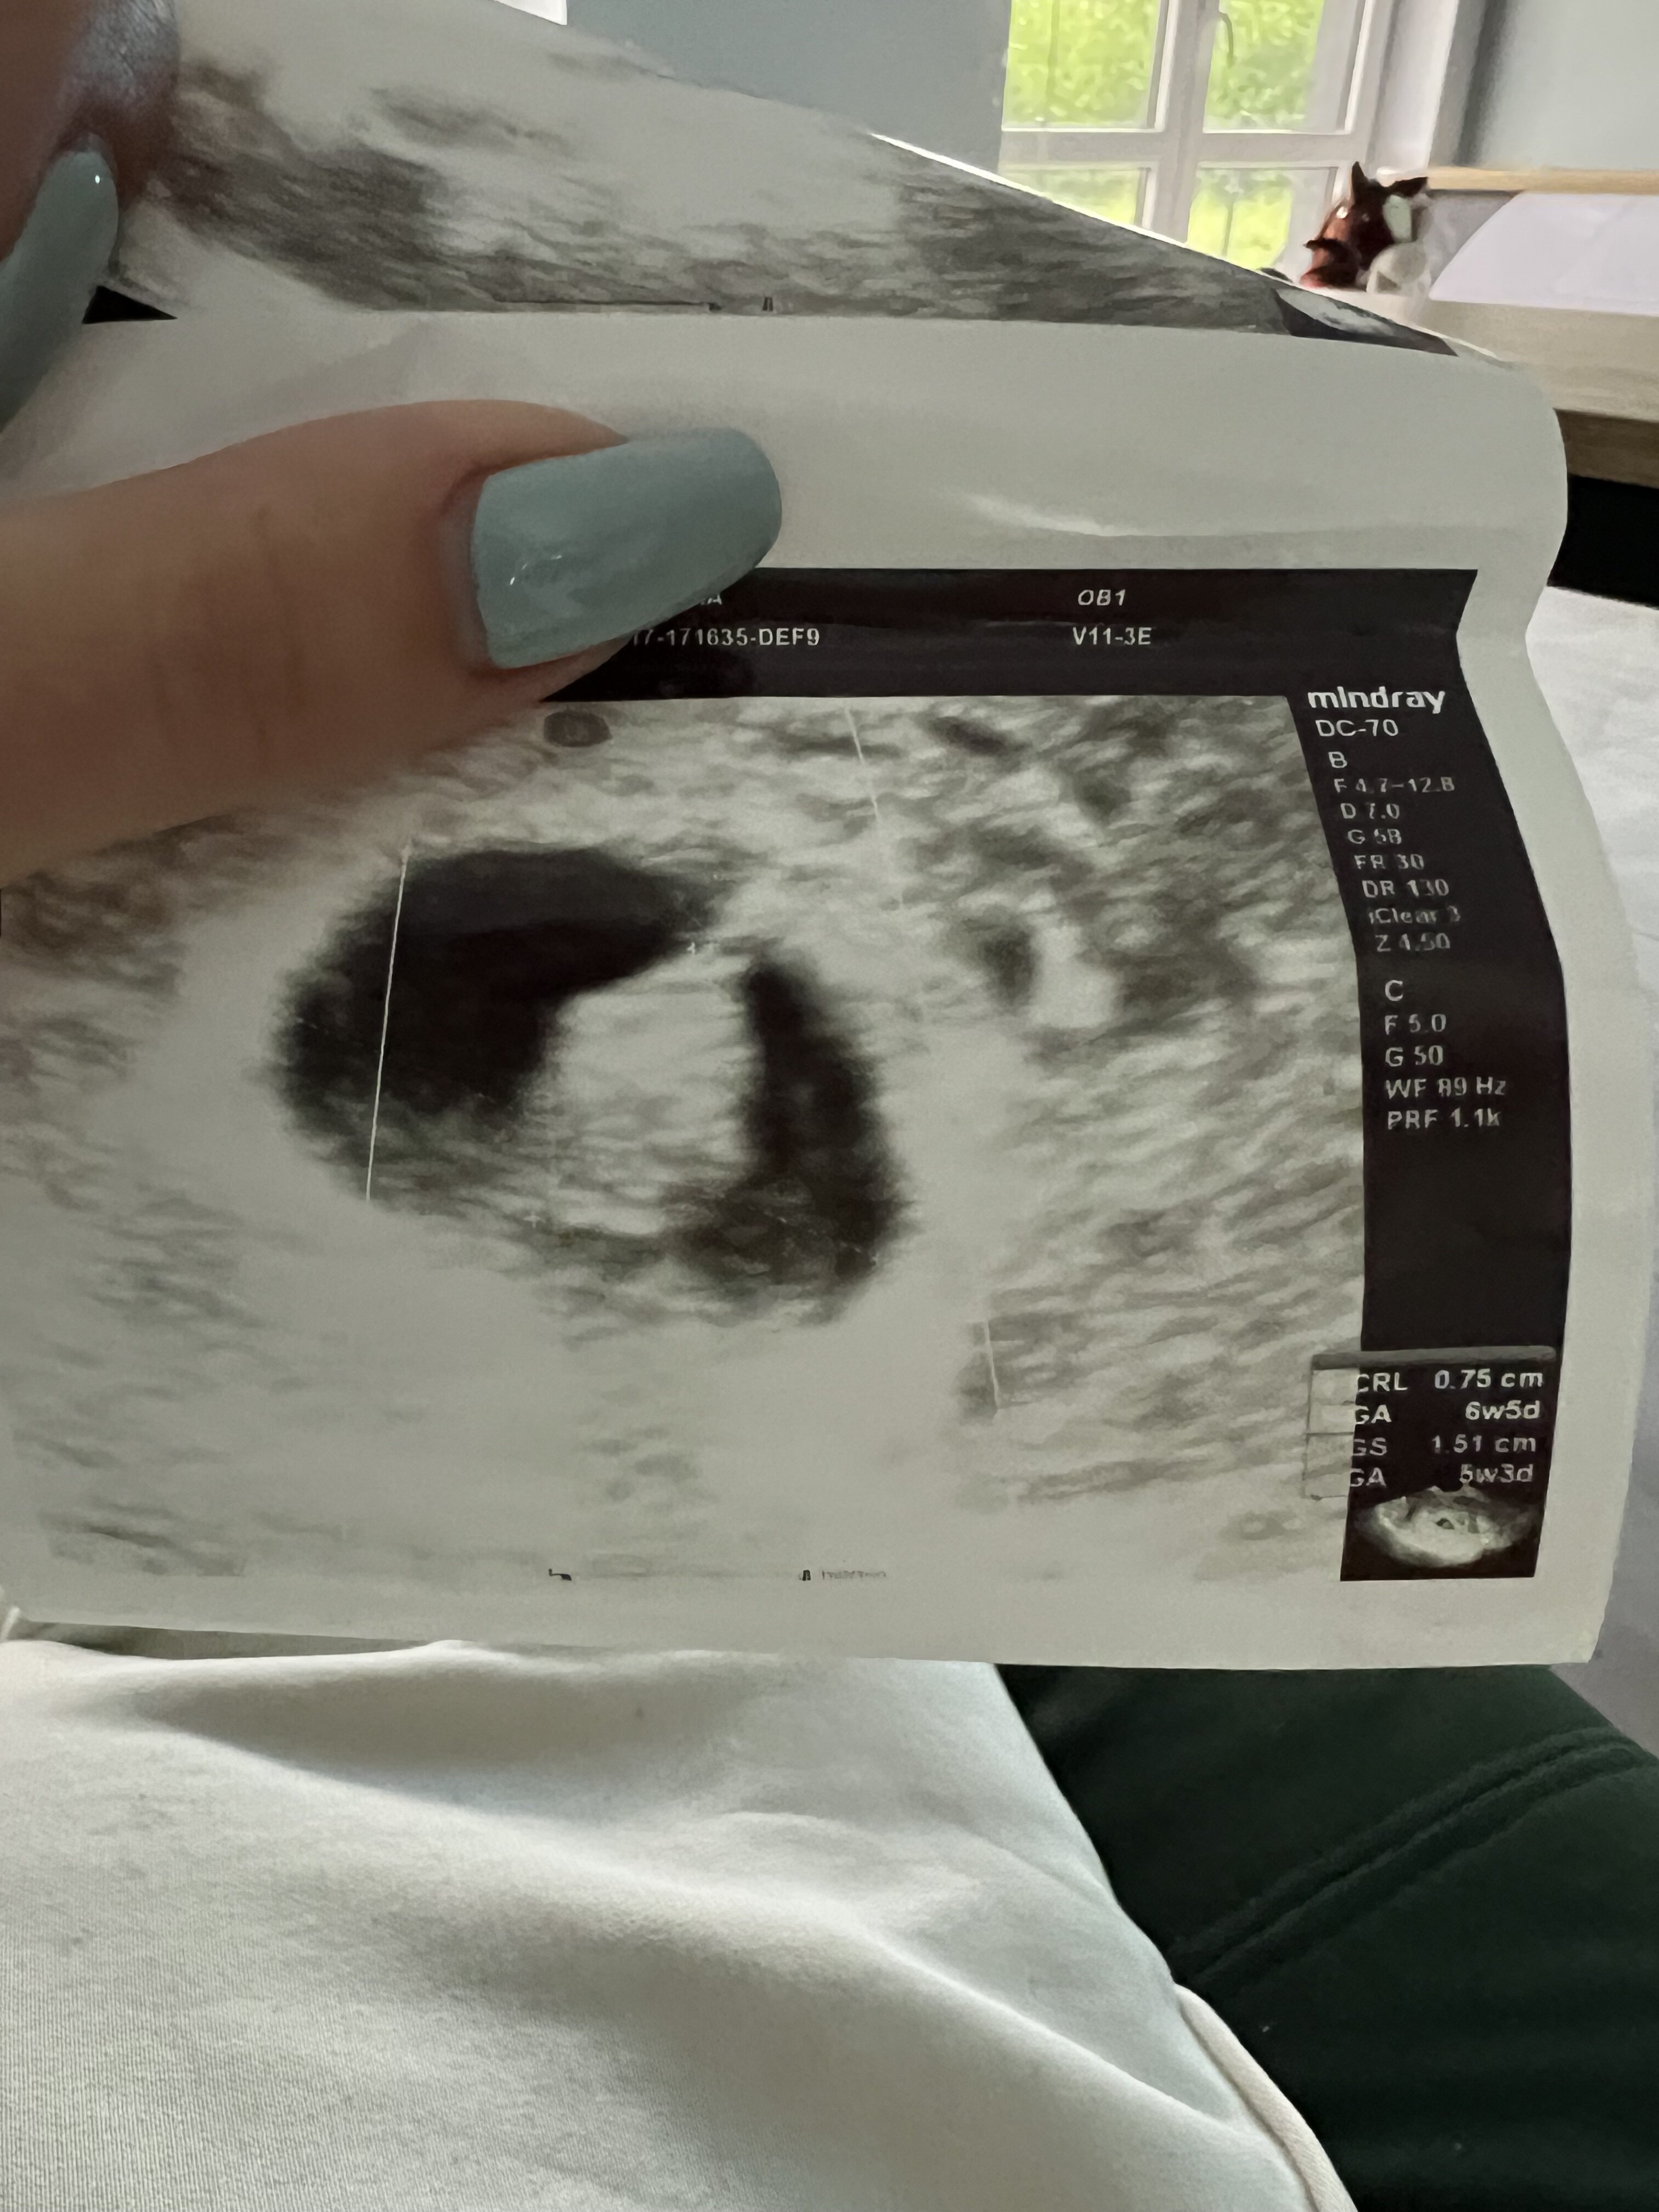

Właśnie wracam od ginekologa i niestety po pierwszej wizycie z płaczem.

Według obliczeń 6tc z czego pęcherzyk płodowy mniejszy od płodu o około tydzień…I najgorsze ze brak echo serduszka ,myślicie ze serce jeszcze może się pojawić? Ginekolog powiedział ze nie widzi takiej szansy